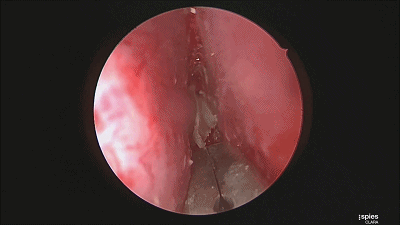

▼切开黏软骨膜后始可开始分离。若剥离子在黏膜与软骨膜之间,软骨膜仍盖于软骨上,则呈柔软红色;若软骨膜已分开,则呈闪光白色的表面。

![]()